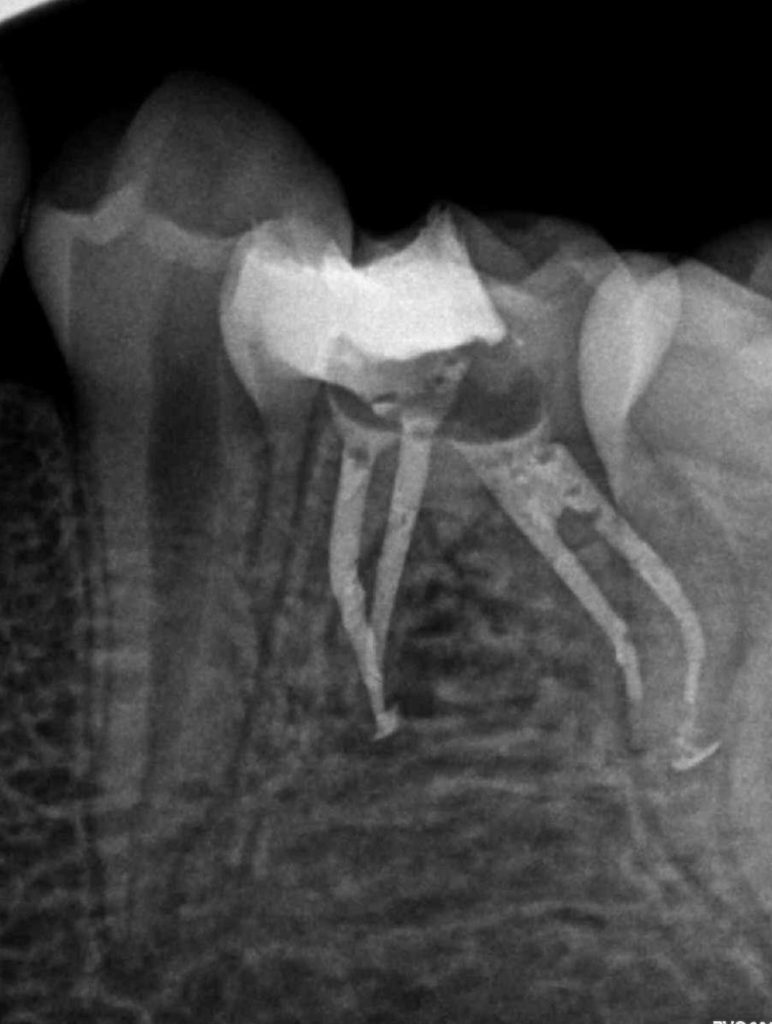

Reco preendo, 2o Molar superior